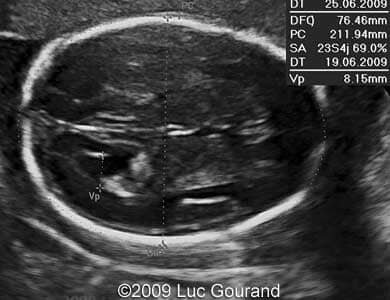

Images 1,2: Image 1 shows an axial plane of the brain, thalami are well separated, cavum septi pellucidi is not seen. Image 2 shows the confluence of the posterior horns of the lateral ventricles.

Case262_1

Case262_2